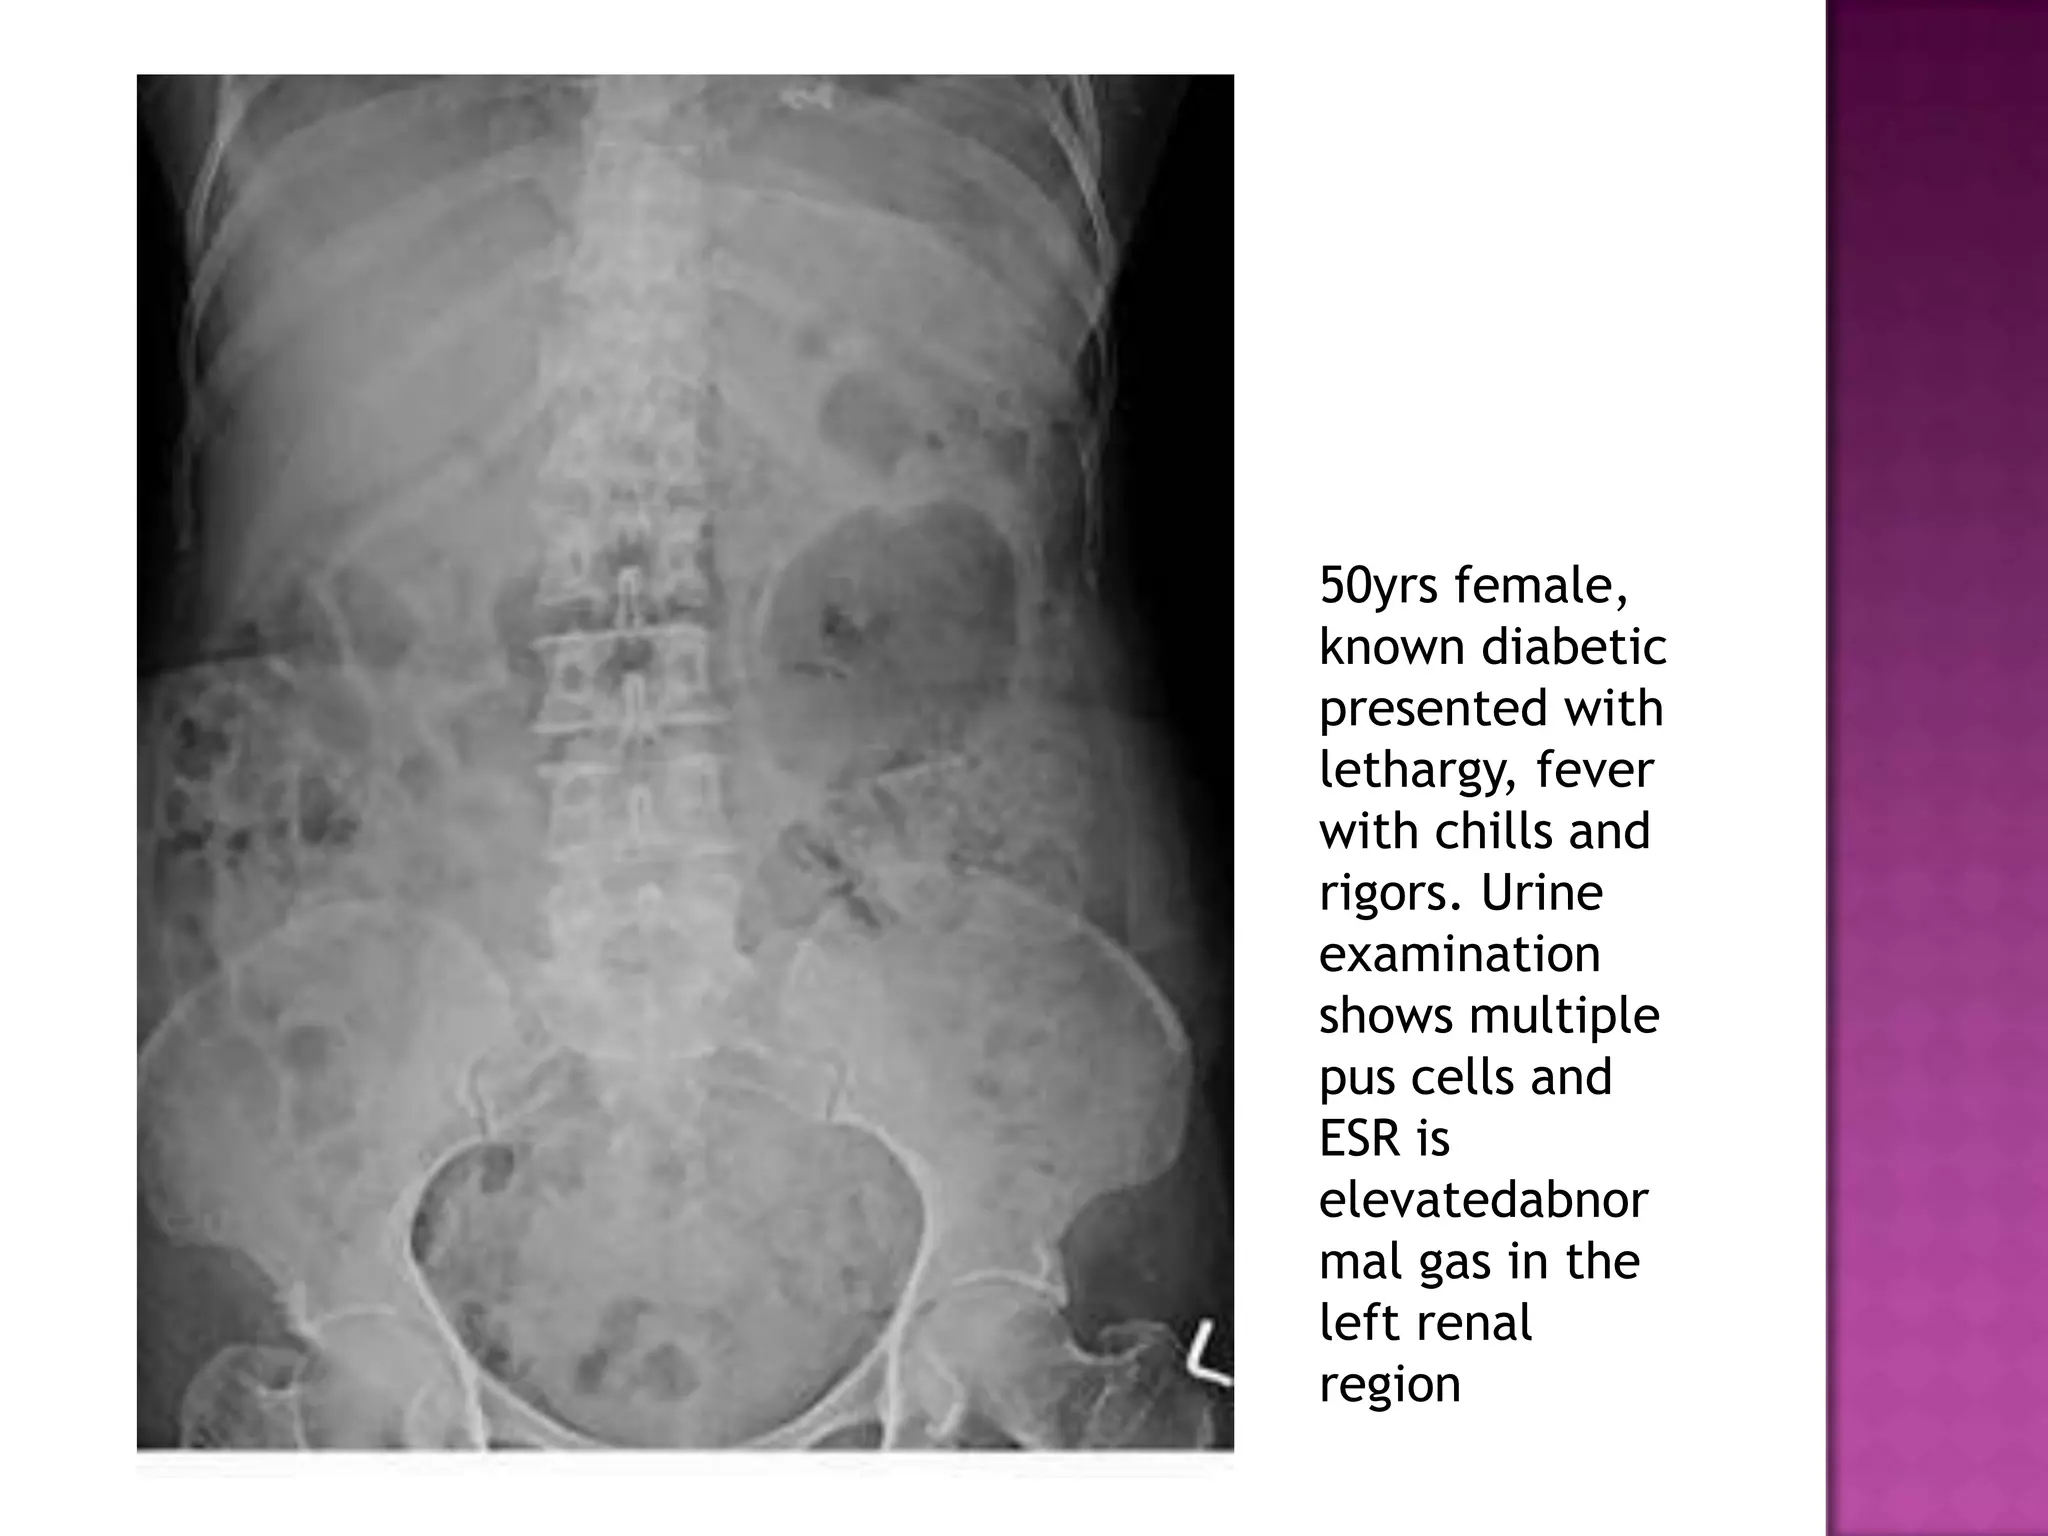

50yrs female,

known diabetic

presented with

lethargy, fever

with chills and

rigors. Urine

examination

shows multiple

pus cells and

ESR is

elevatedabnor

mal gas in the

left renal

region

50yrs female, known diabetic presentedwith lethargy, fever with chills and rigors. Urine examination shows multiple pus cells and ESR is elevatedabnor mal gas in the left renal region